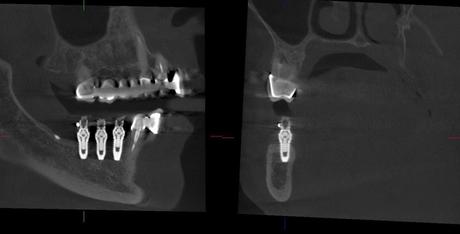

La técnica de regeneración ósea guiada, utilizada para facilitar la formación de hueso en los defectos de los maxilares, se ha empezado a emplear con éxito para la correcta colocación de implantes dentales cuando se precisa un adecuado volumen óseo. La técnica, basada en la bioingeniería, permite unos resultados mejores que el injerto óseo, utilizando otros elementos: un biomaterial y membranas

Antes de su aplicación, el doctor Ciurana recomienda “estudiar el defecto a tratar mediante una radiografía en tres dimensiones con el fin de prever cualquier inconveniente”. La técnica quirúrgica se puede realizar con anestesia local y su duración no supera la hora en los casos más habituales. Una de sus ventajas es que puede realizarse al mismo tiempo que la colocación de los implantes. En estos casos, tras su realización, es preciso liberar la zona de presión y seguir hábitos saludables. Se necesita esperar alrededor de unos cuatro o seis meses a que el defecto se rellene de hueso. Una vez regenerado el defecto el hueso habrá recuperado su función.